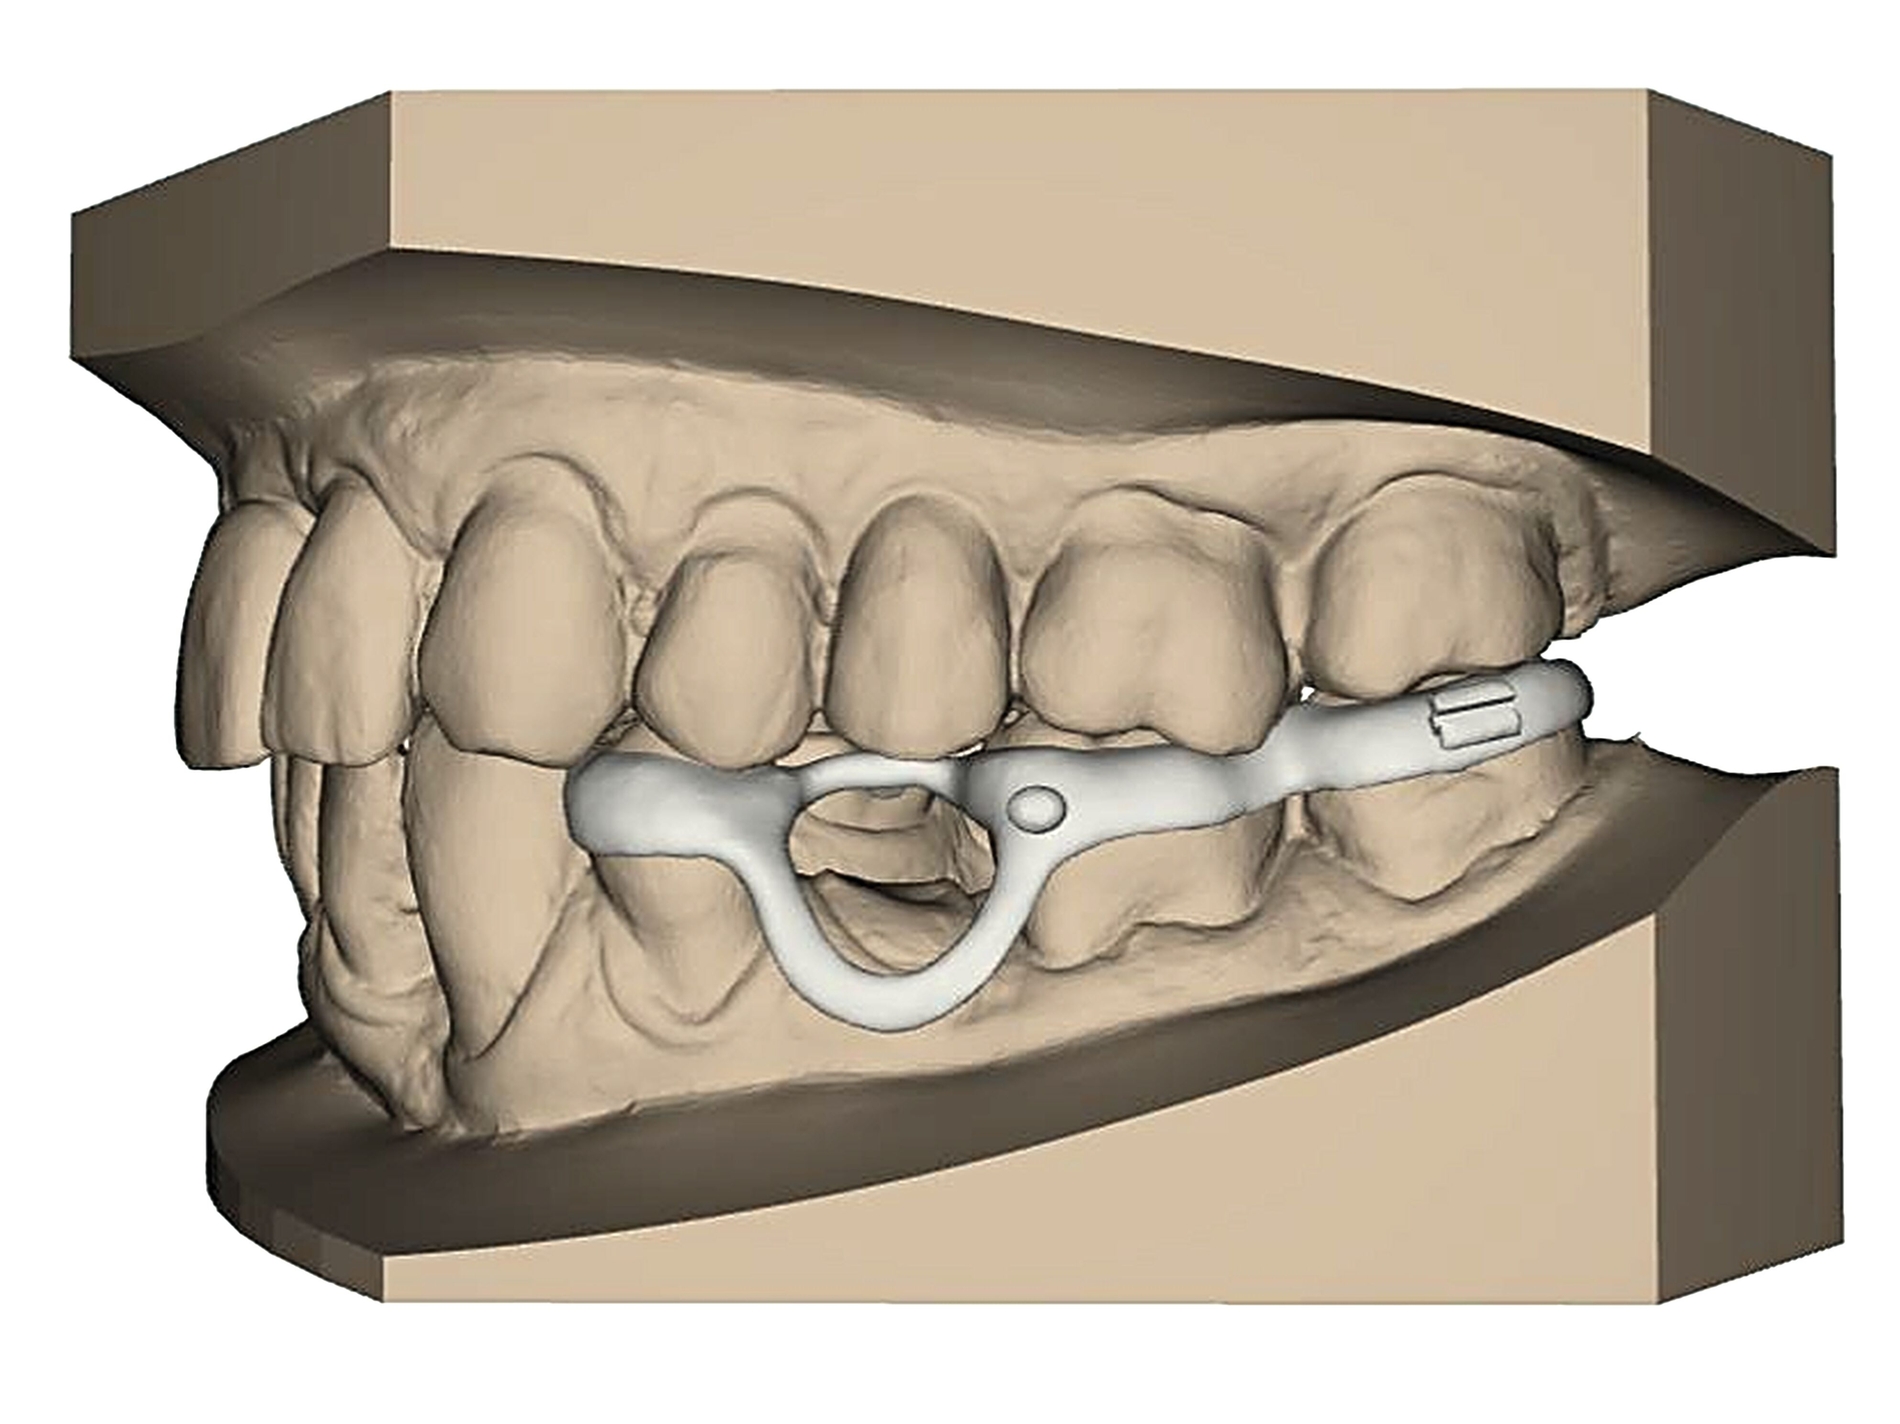

Eine Sonderform der kieferorthopädischen Extrusion ist die kieferorthopädische Extraktion, bei der die gesamte Wurzel langsam und kontrolliert aus der Alveole gehoben und am Ende extrahiert wird. Dieses Verfahren wird insbesondere dann angewendet, wenn ein Implantatbett mit ausreichendem Knochenangebot geschaffen werden soll [Bauer et al., 2019]. Schnelle und langsame Extrusionstechniken können jedoch auch bei einem Patienten kombiniert werden, wenn sowohl Anpassungen des Gingivaverlaufs als auch Veränderungen der Stumpfhöhe zur nachfolgenden Restauration geplant sind (Abbildung 2).

Schnelle kieferorthopädische Extrusionen im Sinne einer präprothetischen Maßnahme können zudem auch im Seitenzahnbereich indiziert sein, wenn für eine nachfolgende Kronenversorgung die notwendigen Voraussetzungen geschaffen werden sollen (ausreichende Stumpfhöhe, Einhaltung der biologischen Breite, Schaffung des Ferrule-Designs) [Gariulo et al., 1961; Juloski et al., 2012; Nugala et al., 2012] unter Einhalten eines Kronen-Wurzel-Verhältnisses von 1:1 [Grossmann und Sadan, 2005] (Abbildung 3).

Durch den Einsatz skelettaler Verankerungshilfen ist es möglich, auch in komplexeren Situationen einen kieferorthopädischen Lückenschluss durchzuführen. Mit digitalen CAD/CAM-Herstellungsmethoden wie dem selektiven Laser-Melting-Verfahren können hochindividualisierte Apparaturen angefertigt werden, die verschiedene Behandlungsaufgaben gleichzeitig adressieren beziehungsweise mit deren Hilfe Kraftvektoren präzise geplant und appliziert werden können.

Zu den weiteren Vorteilen gehören die geringeren Nebenwirkungen auf die Nachbarzähne, die bessere Planbarkeit bei Set-up-basierten Apparaturen, die gute Pflegbarkeit, die einfache Handhabung, die Verkürzung der gesamten Behandlungszeit durch reduzierte Multibracket-Phasen sowie die geringere Beeinträchtigung der orofazialen Ästhetik (Abbildung 5).

Bei Kronen-Wurzel-Frakturen beziehungsweise zervikalen Wurzelfrakturen kann geprüft werden, ob durch schnelle kieferorthopädische Extrusionsmaßnahmen eine nachfolgende Restauration des betroffenen Zahnes wieder ermöglicht wird. Langsame Extrusionen hingegen werden häufig zum Gewebeaufbau oder zur Einstellung eines geeigneten Gingiva- oder Knochenverlaufs eingesetzt. Digital geplante Laser-Melting-Apparaturen ermöglichen es hier, die notwendigen Kraftvektoren besonders präzise bei geringer Stuhlzeit am Patienten anzuwenden.